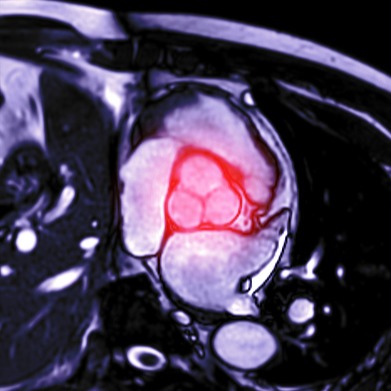

• ecocardiogramma: è una delle tecniche più comuni per la diagnosi della valvola aortica bicuspide. Questa procedura utilizza ultrasuoni per visualizzare il cuore e valutare la struttura delle valvole e la funzionalità;

• risonanza magnetica: la risonanza magnetica fornisce immagini dettagliate delle strutture cardiache e può essere utilizzata per valutare la presenza e la gravità di una valvola aortica bicuspide;